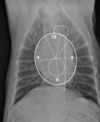

Q

Label the following colored structures

What pathology is going on here?

purple: osseous proliferation

red: patellar ligament angle change

pink: soft tissue opacity increase - cranial aspect of joint

green: lost fascial planes